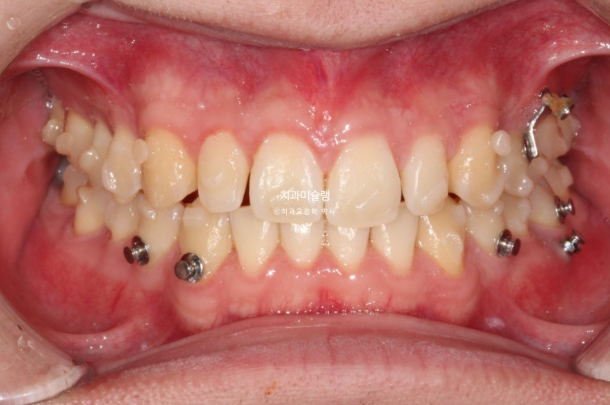

2022년 10월부터 24년 4월까지 1년반동안 첫세트 장치를 모두 낀 후 모습입니다.

24.04

가위교합은 해결이 되었지만 아직 어금니 교합이 긴밀하지 않습니다.

배열은 완벽합니다.

위 아래 중심선은 정확히 맞고

어금니 교합관계도 1급 입니다.

어금니 교합은 좋고 1급 교합관계를 보입니다.

전 후 볼게요

2022.10~2025.06

22.10~25.06

거미스마일과 중심선이 개선이 되었습니다.

깔끔하고 정돈된 미소가 돋보입니다.

한쪽 얼굴이 더 커보이던 것이 차차 개선되어 가는 중입니다.

2년 반의 기간동안 치근흡수는 없고 편측 어금니는 계획대로 사랑니 공간으로 잘 이동했습니다.

치근평행도는 좋습니다.